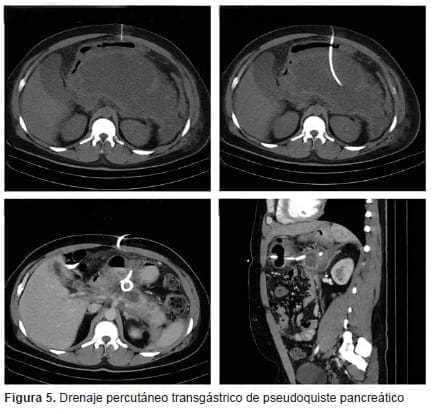

Con relación a la técnica, la mayoría de las intervenciones (86,6 %) fueron procedimientos

de tipo Seldinger guiados por ecografía (66 %) y una menor proporción por TC (34 %). Las

vías de acceso fueron transperitoneal (86,6 %), transgástrica (10,4 %) y transglútea (2,8 %), se gún la ubicación de la colección (figuras 1-5). La duración media del acto quirúrgico fue de 48,7 minutos (desviación estándar de 19,9 minutos).